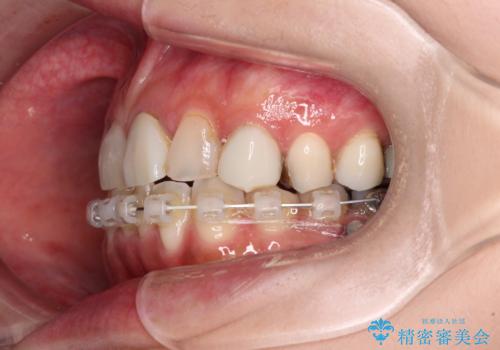

- 長年むし歯を放置してしまっているとのことで来院された患者様です。

神経が除去されている歯、根管治療の必要な歯、むし歯の非常に大きな歯に対してオールセラミッククラウンにて補綴治療を行うこととしました。

インプラント部は治癒待ちの期間が長くなるため、その期間を利用して下顎の叢生を解消し、より理想的な咬み合わせで補綴治療を行うこととしました。

途中通院されなかった時期が何度かあったため、初診から4年以上の年月がかかりましたが、比較的スムーズに治療を進めることができました。

下顎前歯の歯列を整えたことで、上顎前歯の咬み合わせが安定し、自然な口元に仕上げることができました。